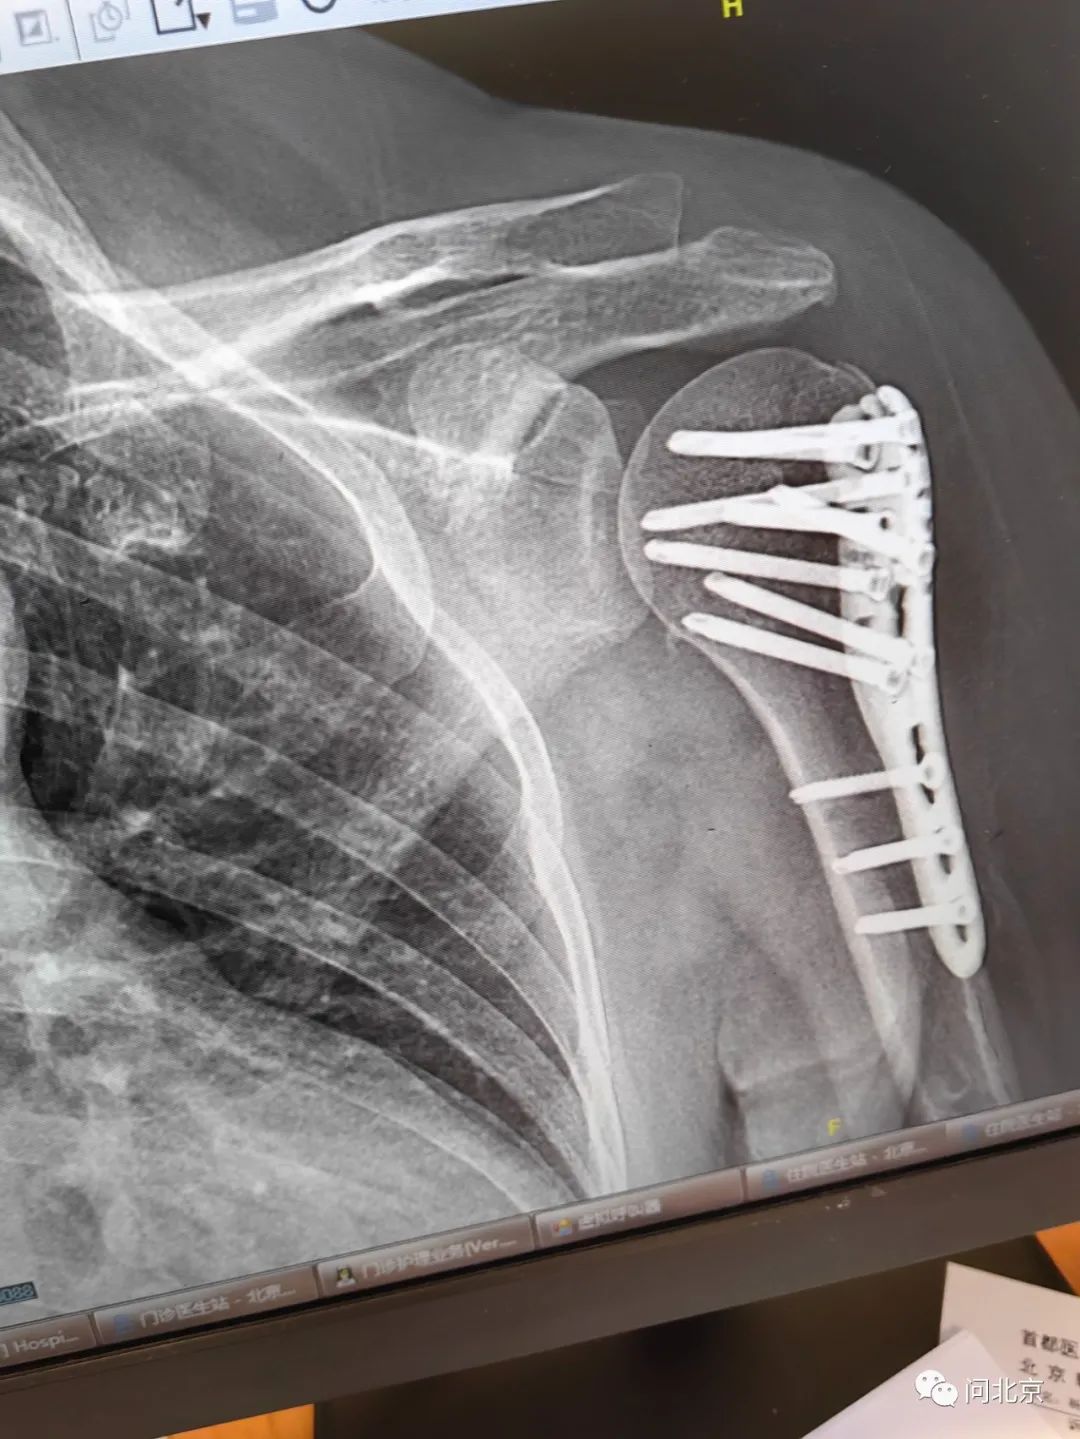

張女士:左邊的肱骨骨折,做手術了,我現(xiàn)在(身體)里邊一塊鈦合金板子11個大釘子,要休息最起碼就得半年,一共花了藥費加住院費就5萬多塊錢。

圖片

張女士手臂骨折術后/受訪者供